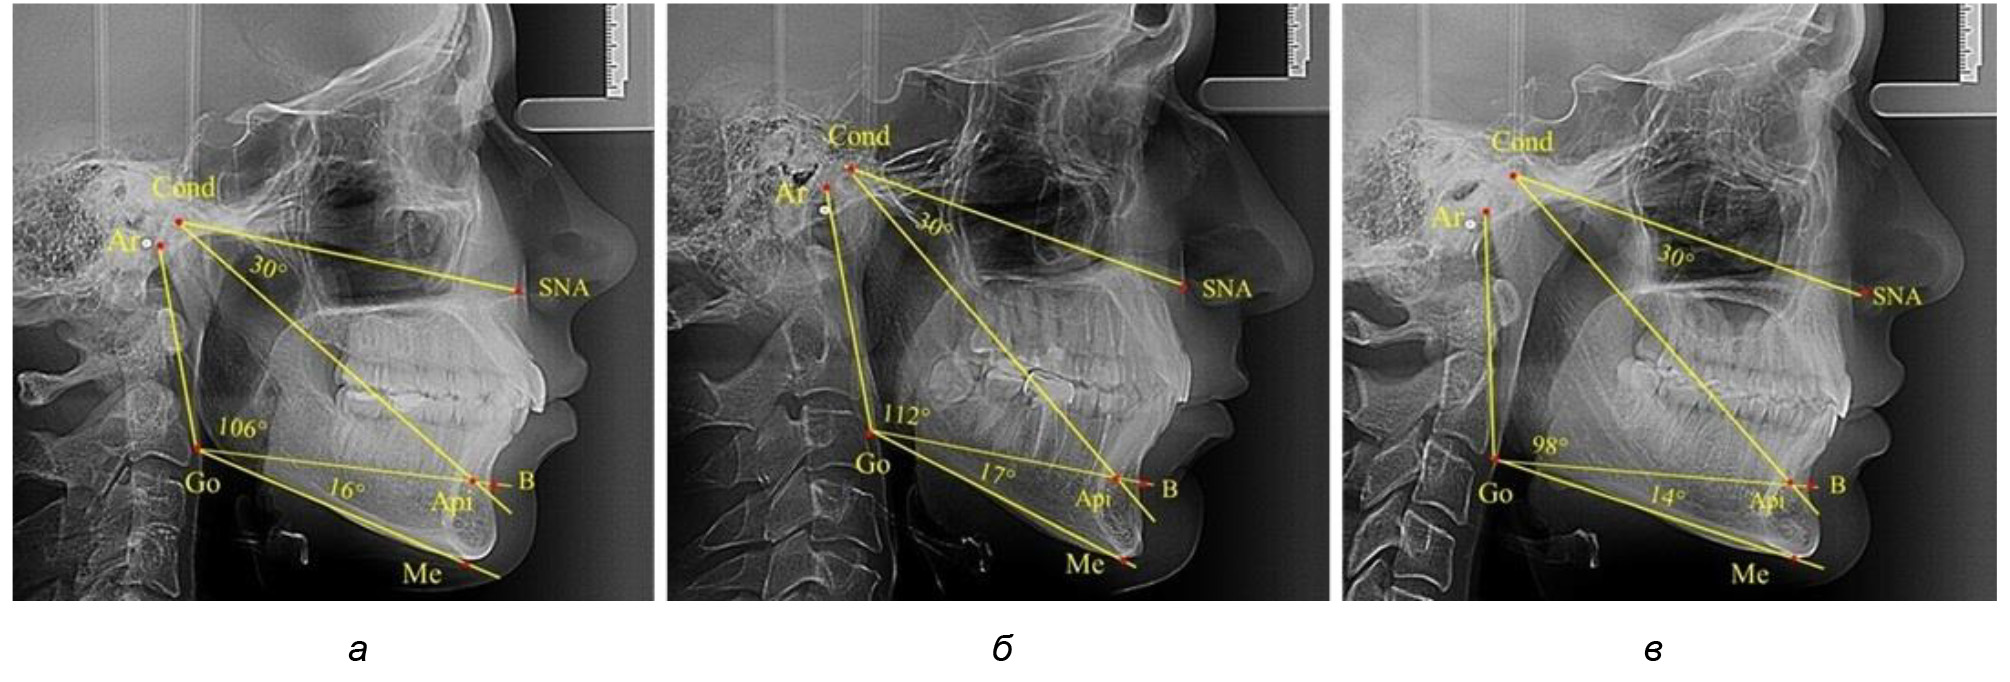

Проведен анализ 28 ТРГ молодых пациентов с физиологической окклюзии. На 13 рентгенограммах были признаки нейтрального роста лица, у 6 человек был вертикальный тип, а у 9 – горизонтальный тип лица.

В результате исследования телерентгенограмм людей в периоде сформированного постоянного прикуса выявлено, что величина угла гнатической части лица SNA-Cond-Api в среднем по группе составил (29,96 ± 0,84)°. При анализе рентгенограмм с разными типами нижнечелюстного угла Ar-Go-Me достоверных различий величины угла гнатической части лица нами не отмечено и при физиологической окклюзии показатели варьировали от 27 до 33°, что определяло оптимальные параметры гнатического отдела лица.

В то же время нижнечелюстной угол варьировал в широких пределах, в частности от 112 до 127°, и его средние значения при физиологическом прикусе составляли (120,57 ± 1,43)°. При этом составляющие части нижнечелюстного угла имели различия. Так, показатель угла Ar-Go-Api варьировал от 110 до 117°, при средних значениях – (107,12 ± 1,73)°. Величина угла Api-Go-Me составляла в среднем (13,56 ± 1,09)° при минимальных значениях 6° и максимальном показатели 19°. Анализируя параметры нижнечелюстного угла на телерентгенограммах с различными типами нижнечелюстного угла, выявлено, что у людей с нейтральными типами угла (в пределах от 119 до 123°) средний показатель был (121,83 ± 0,62)°. Величина угла Ar-Go-Api составила (107,89 ± 1,62)°, а угол Api-Go-Me был (13,83 ± 1,12)°.

При вертикальном типе нижнечелюстного угла его средние значения составили (125,51 ± 0,44)°, и достоверно отличалась от показателей людей с нейтральными значениями нижнечелюстного угла. Величина угла Ar-Go-Api составила (115,49 ± 2,14)°, а угол Api-Go-Me был (13,97 ± 1,26)°.

Для горизонтального типа роста было характерно достоверное р ˂ 0,05 уменьшение нижнечелюстного угла до (115,57 ± 0,56)°. Величина угла Ar-Go-Api составила (102,71 ± 1,62)°, а угол Api-Go-Me был (12,86 ± 0,74)° (рис. 3).

Рис. 3. Особенности ТРГ при нейтральном (а), вертикальном (б) и горизонтальном (в) типе угла нижней челюсти в постоянном прикусе

Таким образом, вне зависимости от величины нижнечелюстного угла, показатели угла гнатической части лица были в пределах 30°, что может расцениваться в качестве оптимального физиологического показателя параметров гнатической части лица. Анализ ТРГ проведен у 31 ребенка в различные периоды дентального онтогненеза, включая прикус молочных зубов и различные группы прорезывания постоянных зубов.